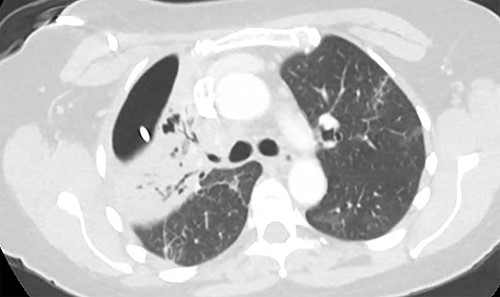

As the patient lived several hours away from the closest hospital, we obtained a second post-operative chest CT to ensure that she had no additional collections and to establish a new baseline. This demonstrated a 4 cm collection in the subcutaneous space. We aspirated the fluid, which showed no growth. The patient was discharged on a course of oral moxifloxacin. A repeat chest CT 4 weeks after Clagett closure was obtained and showed improved aeration of the right upper lobe (Fig. 4).